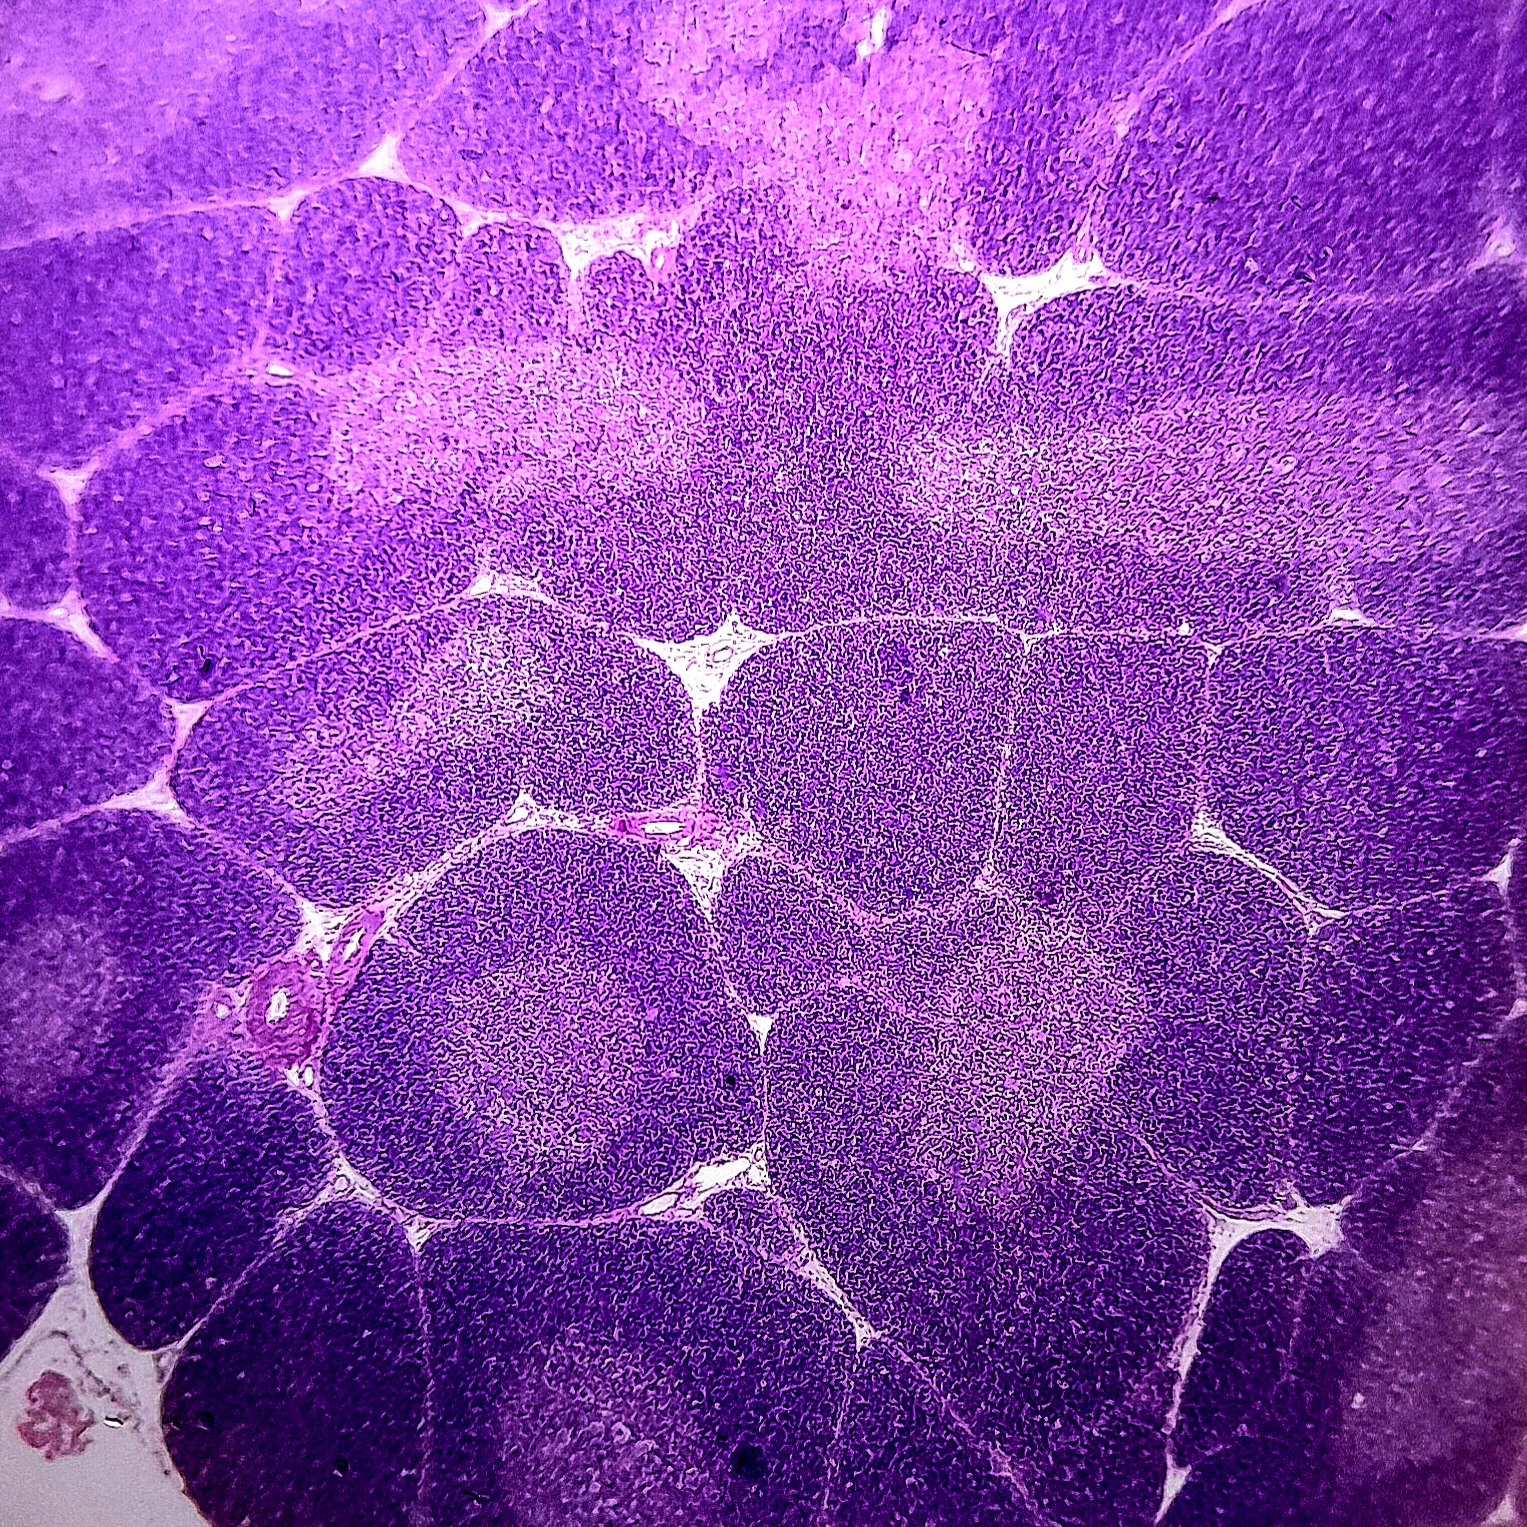

Sistema Linfático

O sistema linfático é uma rede complexa composta por vasos linfáticos, linfonodos e órgãos linfoides, desempenhando um papel crucial na defesa imunológica, removendo patógenos e células anormais, contribuindo para a defesa do organismo, além de participar da produção, ativação, maturação e destruição de linfócitos, que são fundamentais na resposta imune adaptativa.